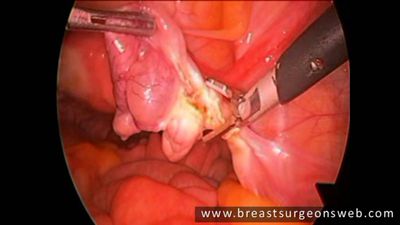

Ooforectomía laparoscópica presentando las tijeras HARMONIC ACE®+7 con hemostasia avanzada

Total Laparoscopic Hysterectomy featuring HARMONIC ACE®+7 Shears by Dr. Kondrup

Tijeras quirúrgicas HARMONIC ACE®+7

Ooforectomía laparoscópica presentando las tijeras HARMONIC ACE®+7 con hemostasia avanzada